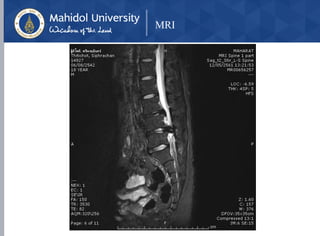

MRI

Diagnostic Imaging

• X-Ray : L-S spine AP, lateral

• loss of lordosis (spasm)

• loss of disc height

• lumbar spondylosis

• MRI

• Modality of choice

• Indications for obtaining an MRI

• pain lasting > 1 month and not responding to

nonoperative management

• Red flags are presentenerative changes